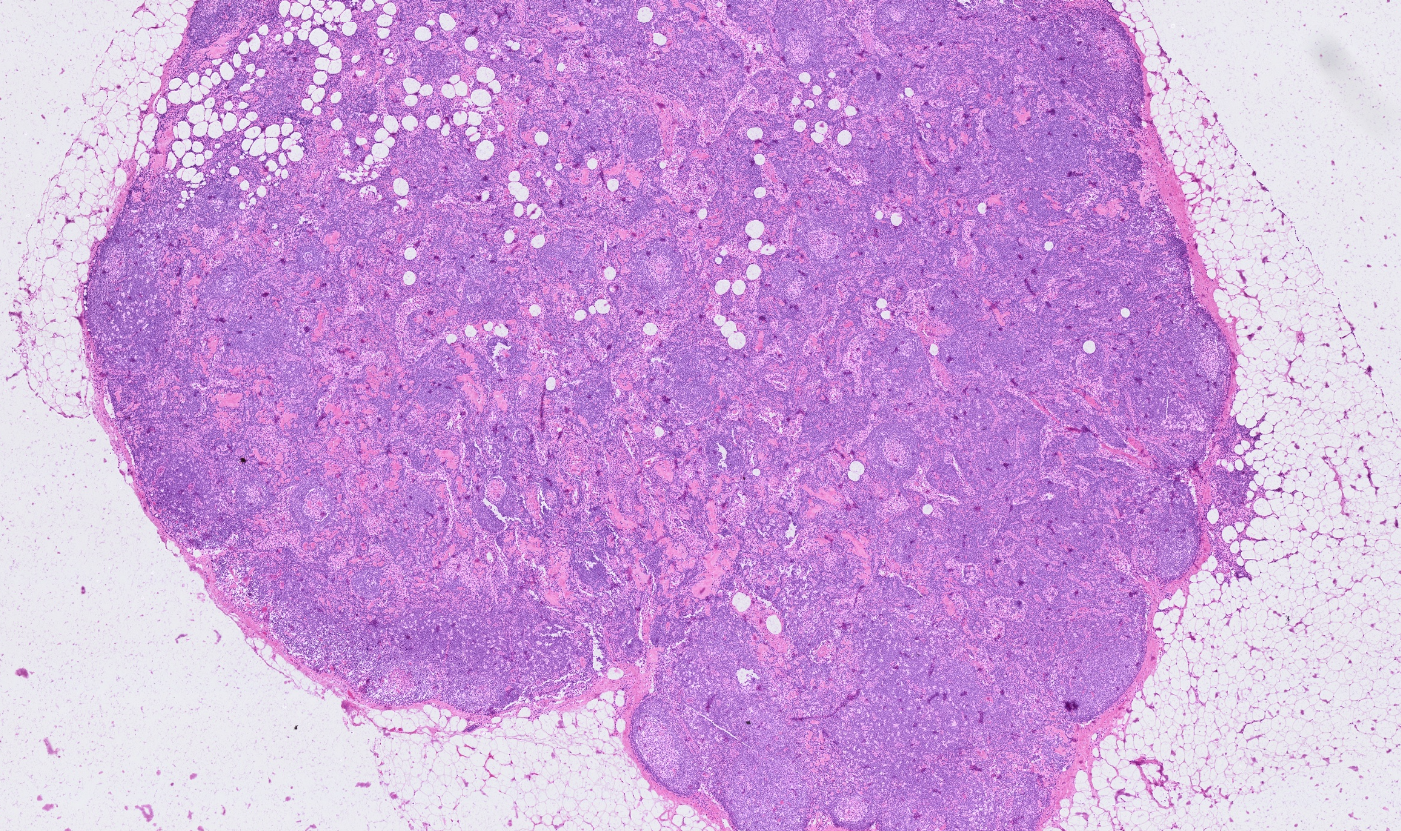

Applicability across many tissue types

The segmentation module is designed to generalize across a wide range of biological tissues. Below are representative benchmark results based on 10x Genomics demo datasets:

Lymph node